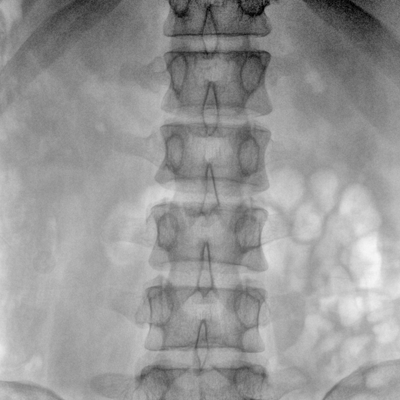

大尺寸動態(tài)平板探測器,高DQE、低噪聲、圖像清晰。采用多分辨率圖像增強(qiáng)處理技術(shù),不同部位不同圖像處理算法,滿足客戶多樣化的需求。